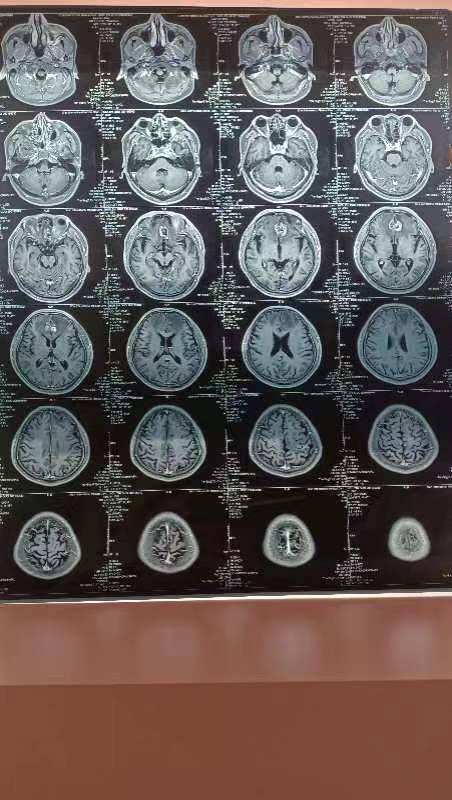

第三次伽马刀后复查

去年9月底做的伽马刀,因为新冠一直拖到现在才复查。肺部依然保持原样,脑部有病灶坏死的组织。对比上次片子,有脑水肿。医生建议挂贝伐珠单抗一次四支,两次后复查。吃3922第二十个月了,希望长长久久的吃下去。